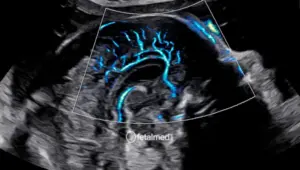

Como é realizada

Guiada por ultrassom, uma agulha é introduzida através do abdômen materno até a placenta. Uma pequena amostra de tecido é aspirada. O procedimento dura poucos minutos e é realizado em ambulatório.